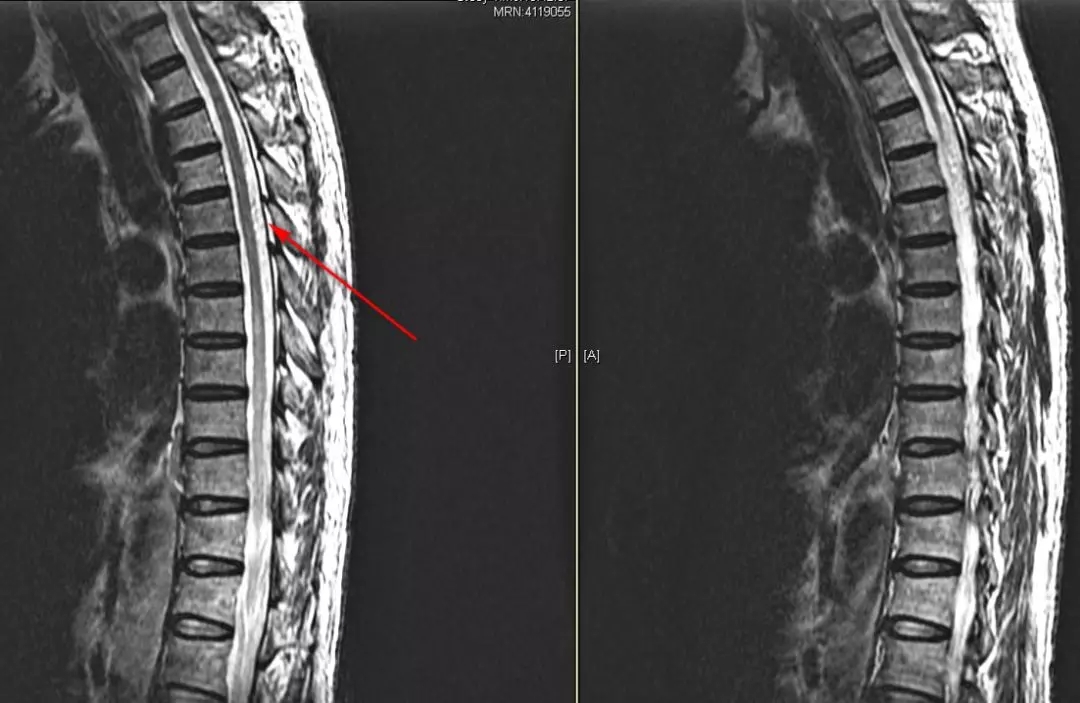

基本情况:王某,男,61岁。入院时间:2019年8月9日。主诉:双下肢麻木无力半年。

现病史:患者半年前无诱因出现双下肢麻木、无力,逐渐向上延伸,左下肢无力显著,伴行走不稳,随后出现大小便困难。8月3日给予糖皮质激素治疗后,双下肢麻木无力加重。

查体:双下肢浅感觉减退,左侧膝反射阳性,闭目难立征阳性。